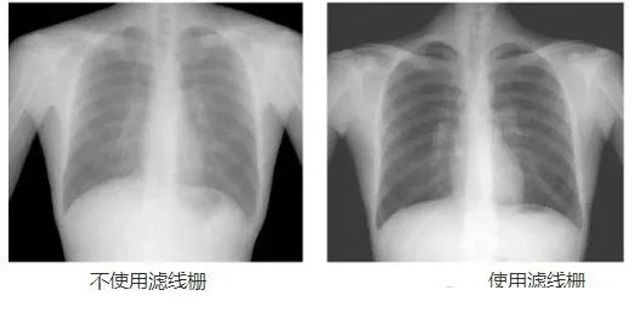

DR影像X射線在醫(yī)學檢查成像有著廣泛的使用。但是它的散射線影響成像質(zhì)量問題。濾線柵的發(fā)明使用很好的解決了這個問題,構造簡單鉛條粗,密度和柵比規(guī)格單一,能減散射線但吸收較多原發(fā)射線。伴隨這醫(yī)療影像設備技術的發(fā)展,這個濾線柵的工藝制造技術有改進,鉛條變薄,柵密度和柵比有更多的選擇。特別是材料方面有新組合,填充物也依不同成像要求優(yōu)化。特別是移動DR這類型的DR設備的出現(xiàn),濾線柵也設計成立方便拆卸形的,方便使用。被照體情況決定是否使用,更好平衡成像質(zhì)量與射線劑量。

放置方面:置于人體與片盒間,聚焦面朝向X線入射方向,X線焦點放鉛條會聚線上,不能反置,X線中心對準濾線柵中心,左右偏移不超3cm,傾斜X線管要與鉛條排列方向平行。攝影時焦距改變不超焦距的25%;活動式濾線器運動時間至少長于曝光時間的1/5;因吸收原發(fā)射線要適當增加曝光條件;四肢薄位置一般不用濾線柵;不同千伏對應不同柵比;立位胸片架、乳腺DR攝影等有各自特定濾線柵要求。